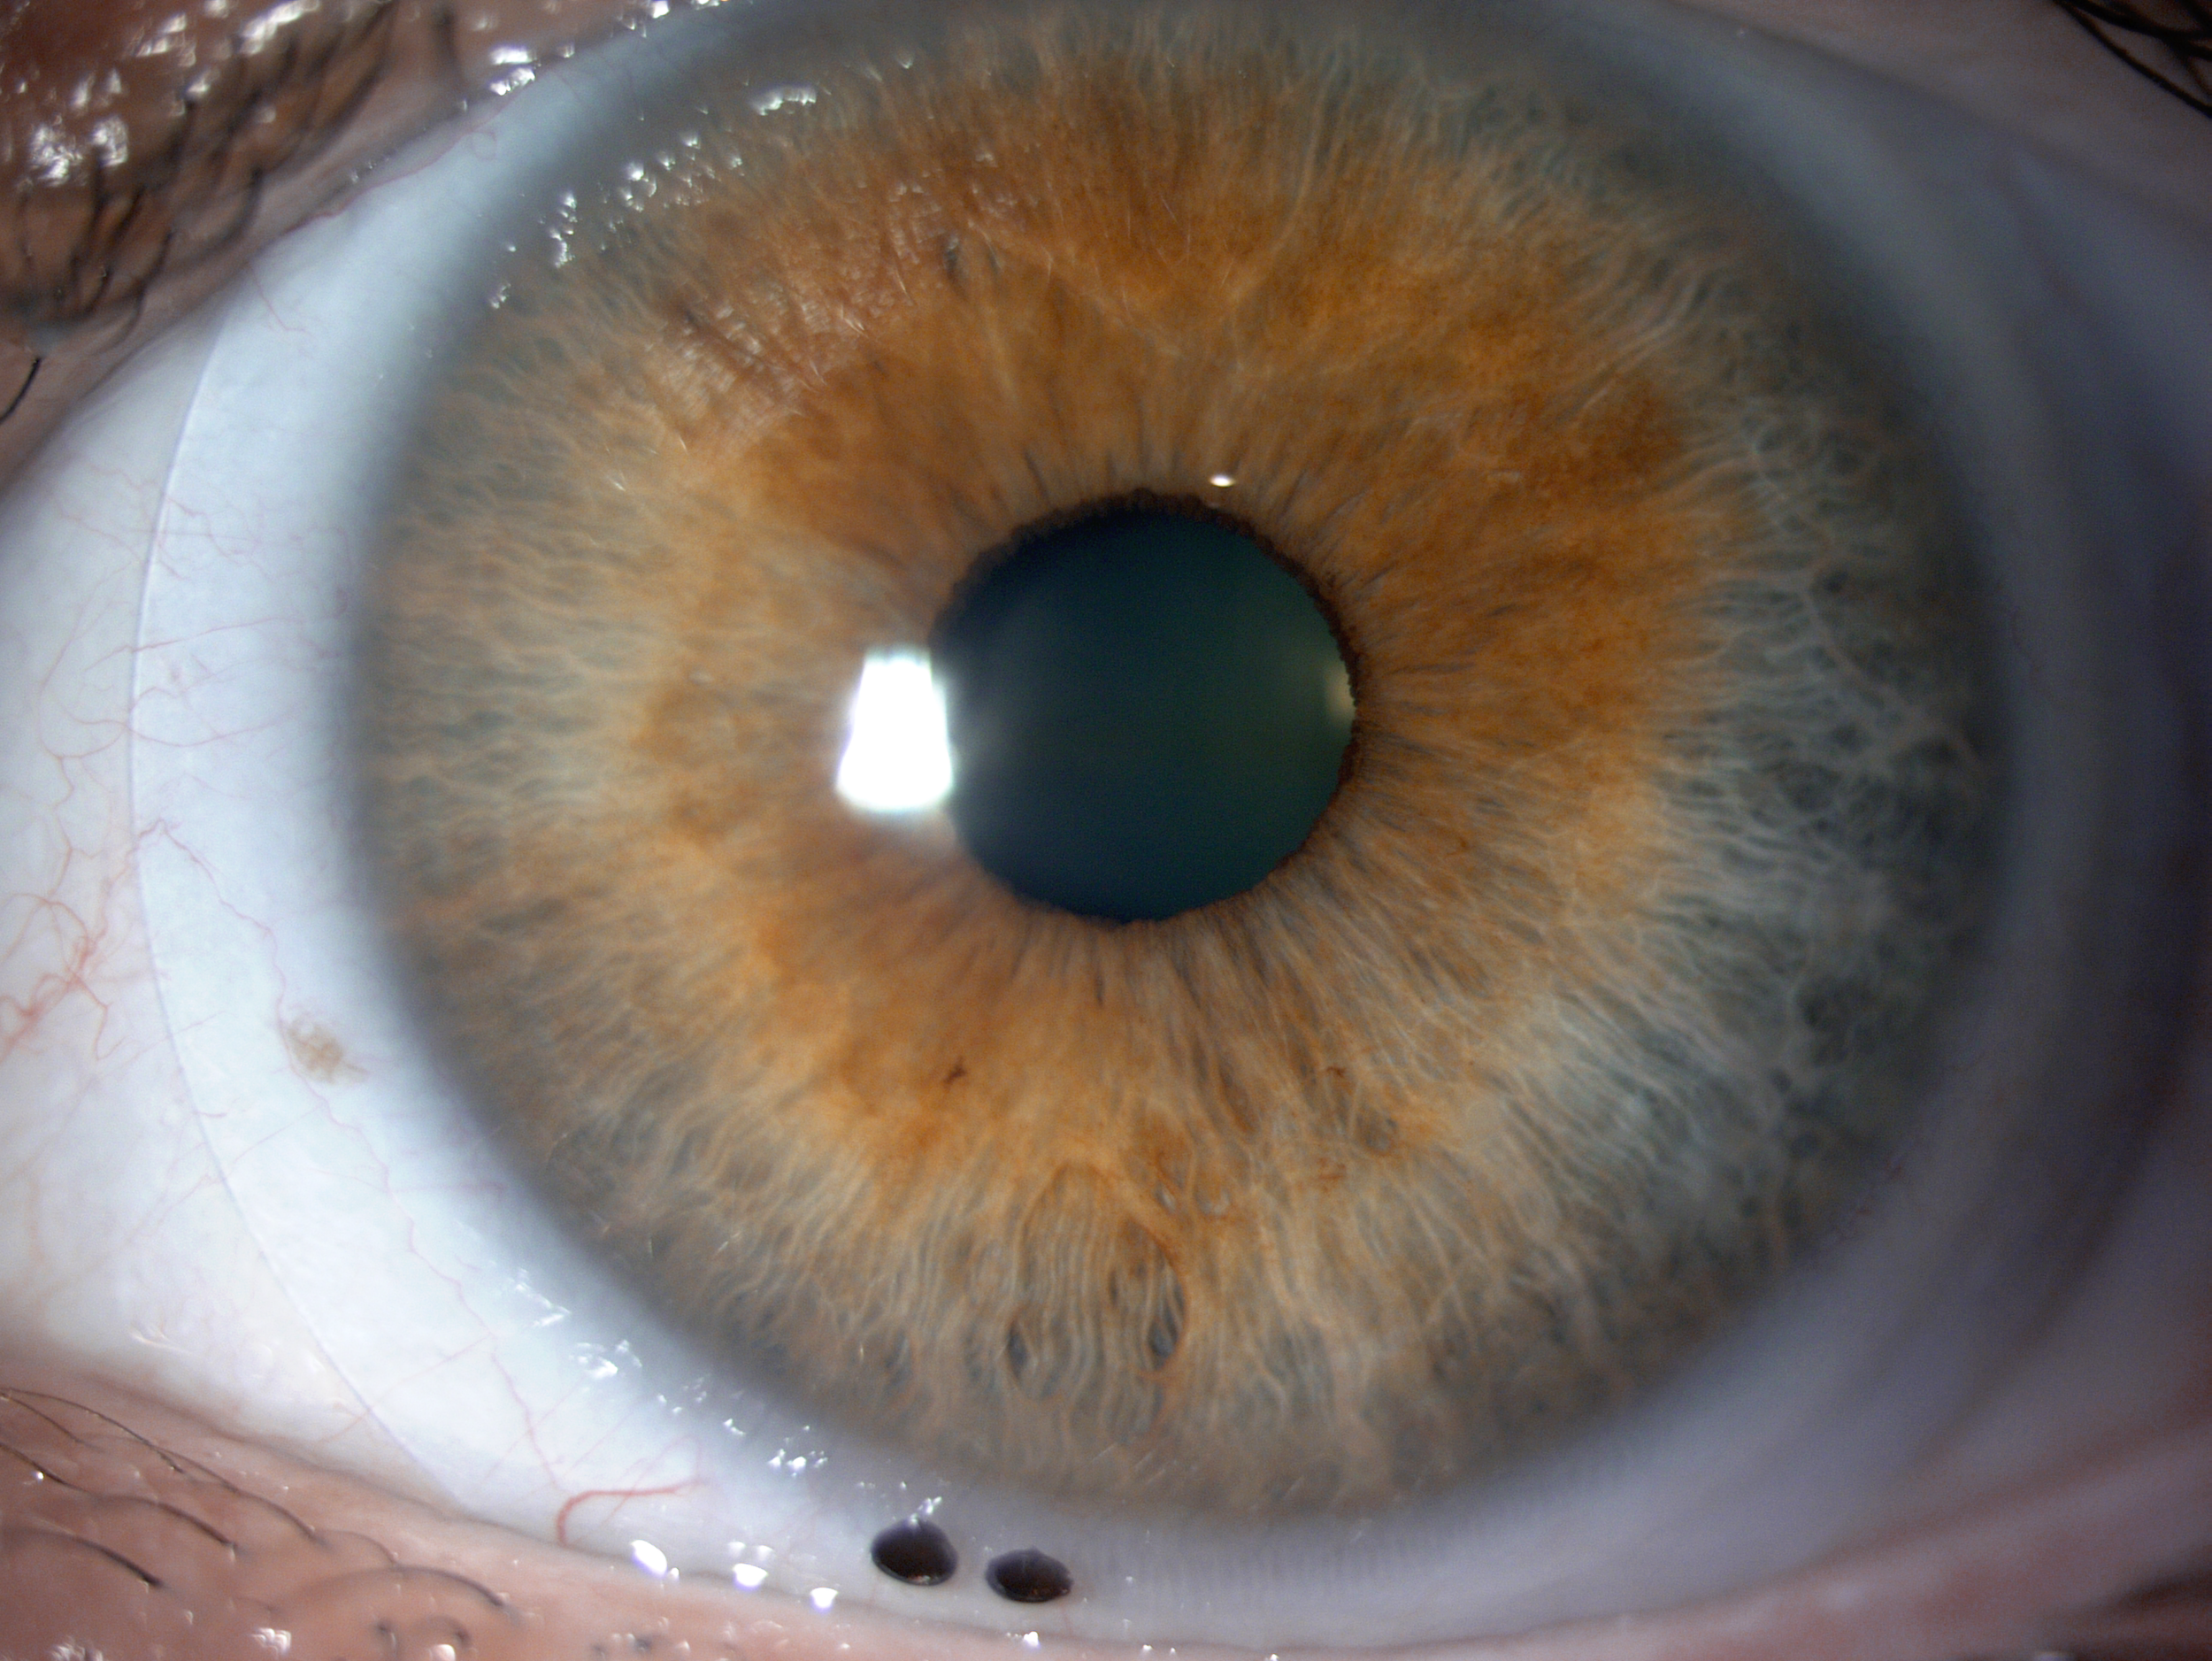

Scleral lenses are large diameter gas-permeable contact lens devices.

Rather than sitting directly on the eye like a traditional soft lens, scleral lenses only touch the sclera (the white part of the eye) and vault entirely over the cornea (the front of your eye - a clear layer of tissue that covers your iris, pupil and lens). This vault - the space between the contact lens and your cornea - is filled with fluid and creates a new, perfect focusing surface.

By vaulting over the eye with fluid, we are able to manage complicated eye conditions such as astigmatism, keratoconus, corneal transplants, severe dry eye, corneal scarring, LASIK complications and more. These lenses can be life changing.

At a scleral lens consultation, we will first learn and discuss your eye health history, take profilometry and topography scans, and discuss your needs. If you are new to scleral lenses, we will place a “demo” scleral lens on your eye(s) to check the vision potential of your eyes, as well as to see if your eyes feel better if your condition is related to dry eyes. If we determine that you are a candidate and proceed with scleral lenses, our doctor Dr. Seif then orders a unique, custom designed lens and adjusts it until the most optimal vision and fit is achieved.

For established wearers, we would assess your current prescription and utilize anterior segment OCT to assess the fit of your current lenses. We may also run aberrometry measurements to see if you would benefit from higher-order aberration correction. We would determine if your current lens design is appropriate healthwise, or if you would benefit from a different lens design.